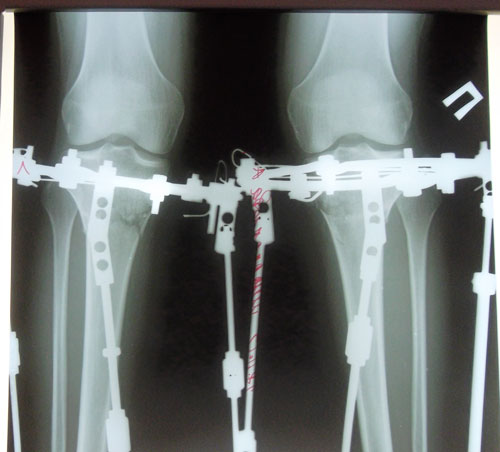

Ножки на 41-й день с момента операции.

рентген в 41 день с момента операции.